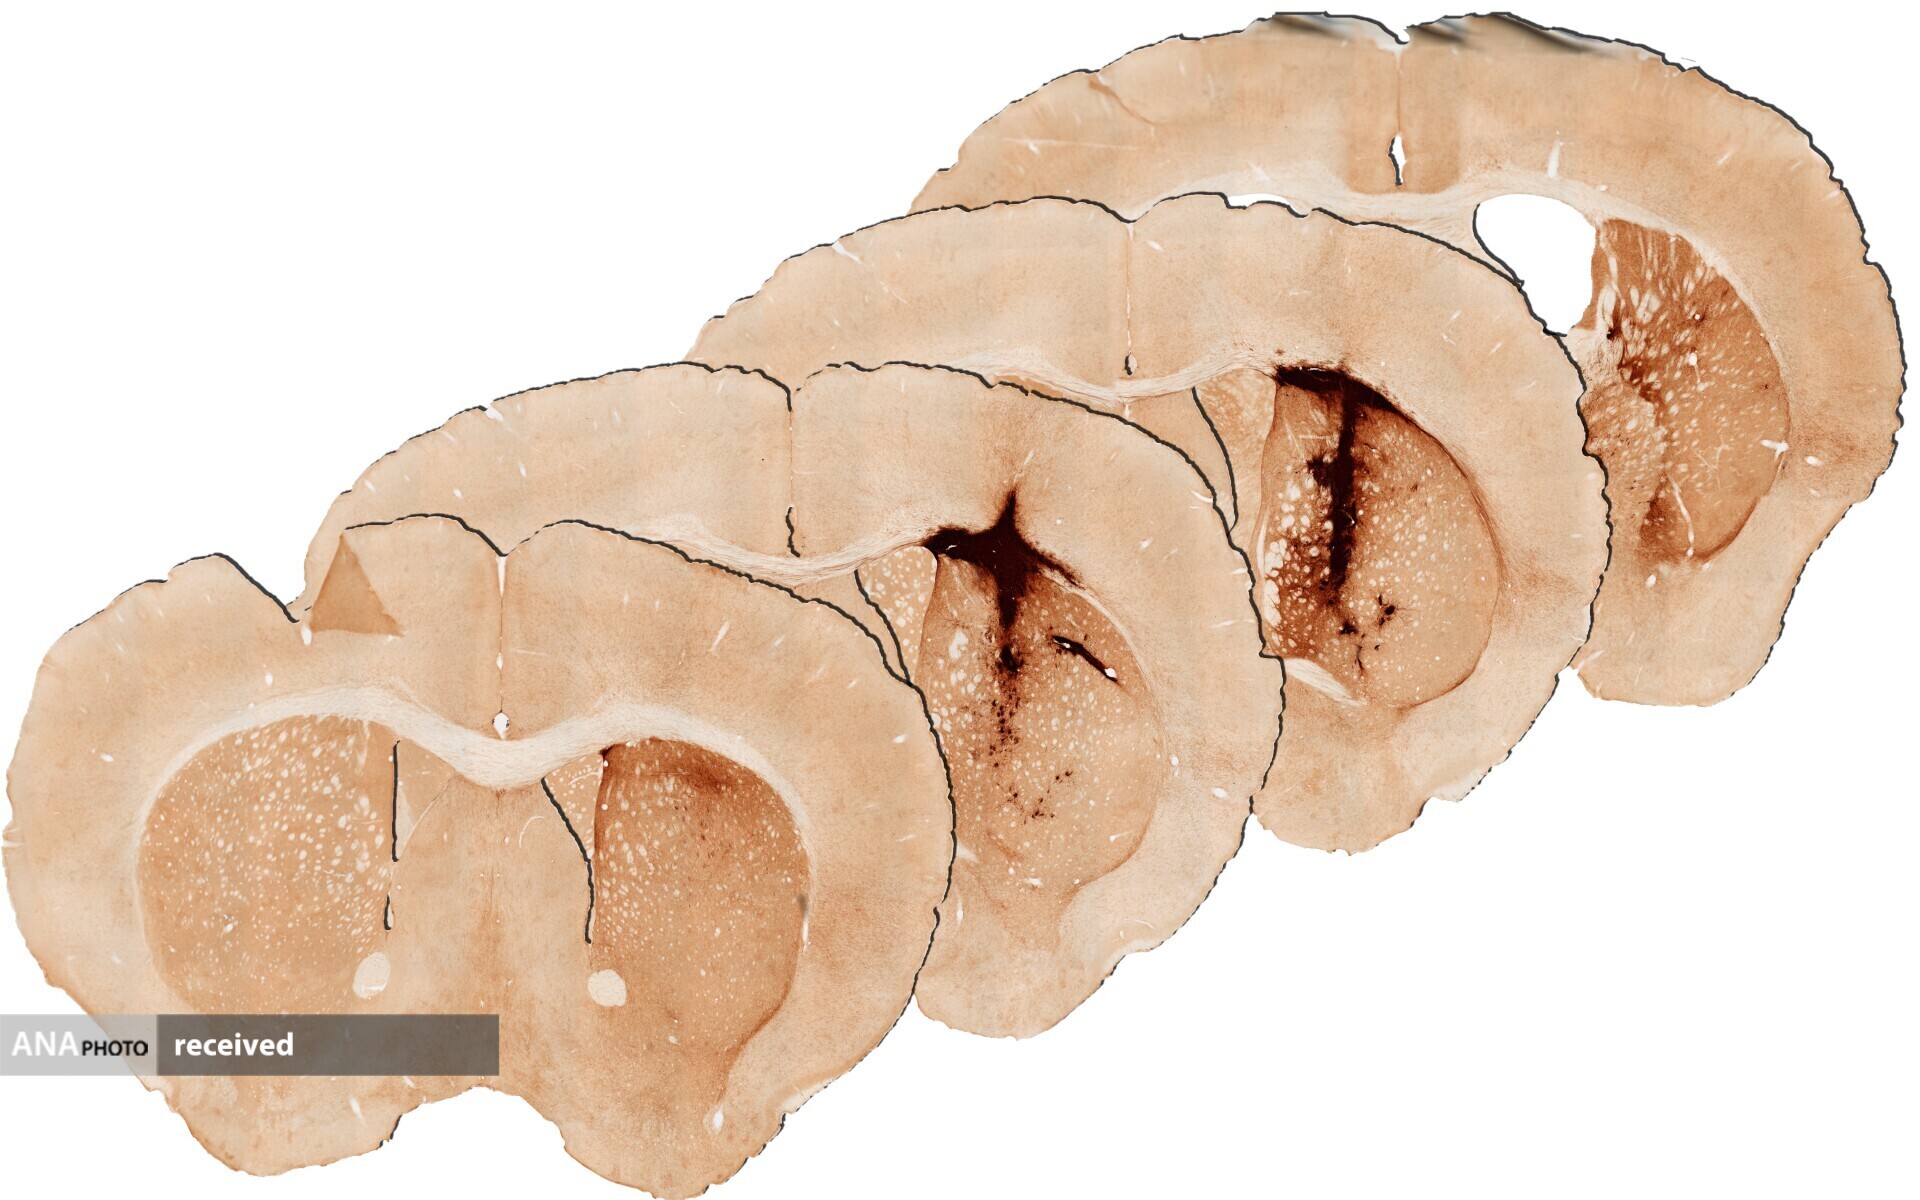

در آزمایشهای بالینی روی موشها، این ژل به تسهیل بقای تعداد بیشتری از سلولها کمک کرد و بعد از چهار هفته نواحی بافت مغز را بهبود بخشید و پتانسیل زیادی برای تکرار در مطالعات انسانی دارد. تصاویر زیر مقطع کاهش قابل توجهی در ماده بافت آسیب دیده (تیره تر) را پس از مدت زمان مشابه در مغز موش هایی که ژل هیبریدی میوگلوبین دریافت کرده اند، نشان می دهد:

تأثیر هیدروژل با میوگلوبین در مغز موش پس از ۲۸ روز

تأثیر هیدروژل بدون میوگلوبین در مغز موش پس از ۲۸ روز

پریش میگوید: «هیدروژل حاوی میوگلوبین و سلول های بنیادی بافت آسیب دیده مغز را ترمیم کرد. تجزیه و تحلیل 28 روز پس از تحویل هیدروژل نشان داد که بقا و رشد سلول های بنیادی جدیدی که برای عملکرد سالم مغز مورد نیاز هستند، در مقایسه با هیدروژل بدون میوگلوبین، به طور قابل توجهی افزایش یافته است.